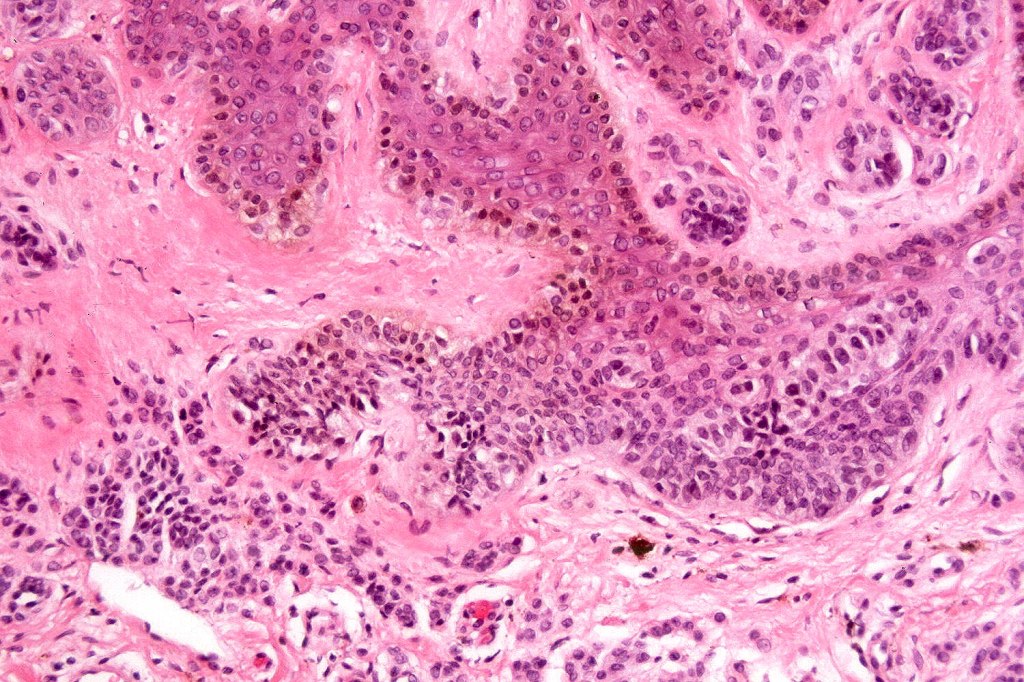

Histological features

•Junctional/compound

•Large dyscohesive nests with retraction artifact, not restricted to the tips of the epidermal ridges

•Heavy pigmentation (sometimes gray/green)

•Bridging common, often over multiple rete ridges

•Variable atypia (can be marked)

•Central pagetoid spread

•Superficial dermal atypia

•Junctional mitoses sometimes present, dermal mitoses+/-, can be multiple but never atypical

•Dermal fibrosis (sometimes lamellar)